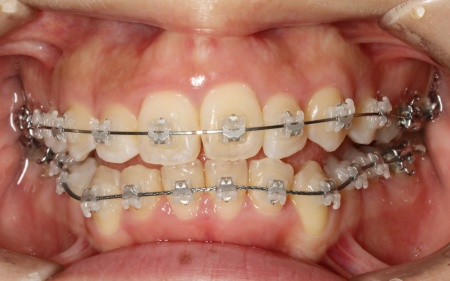

20代女性 ワイヤー矯正とマウスピース矯正を併用したハイブリッド矯正で歯並びを改善した症例

拝見したところ、上下の歯が正しく並ぶためのスペースが足りず、デコボコに生えていました。

とくに、犬歯が正しい歯並びから大きく飛び出した位置に生えており、いわゆる八重歯の状態です。

また、奥歯を噛み合わせた際に上下前歯が噛み合わず隙間ができる開咬(かいこう)も認められました。

続いて、上下の歯の表面に金属のブラケットよりも目立ちにくい「セラミックブラケット」を接着し、ワイヤー矯正を開始しました。